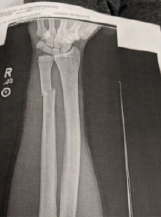

Pictures below----------------------------------------------

Brute Force

"JH was arrested and told he “hit an officer” with his bike and “resisted arrest.” JH was booked and held for about 18 hours. "